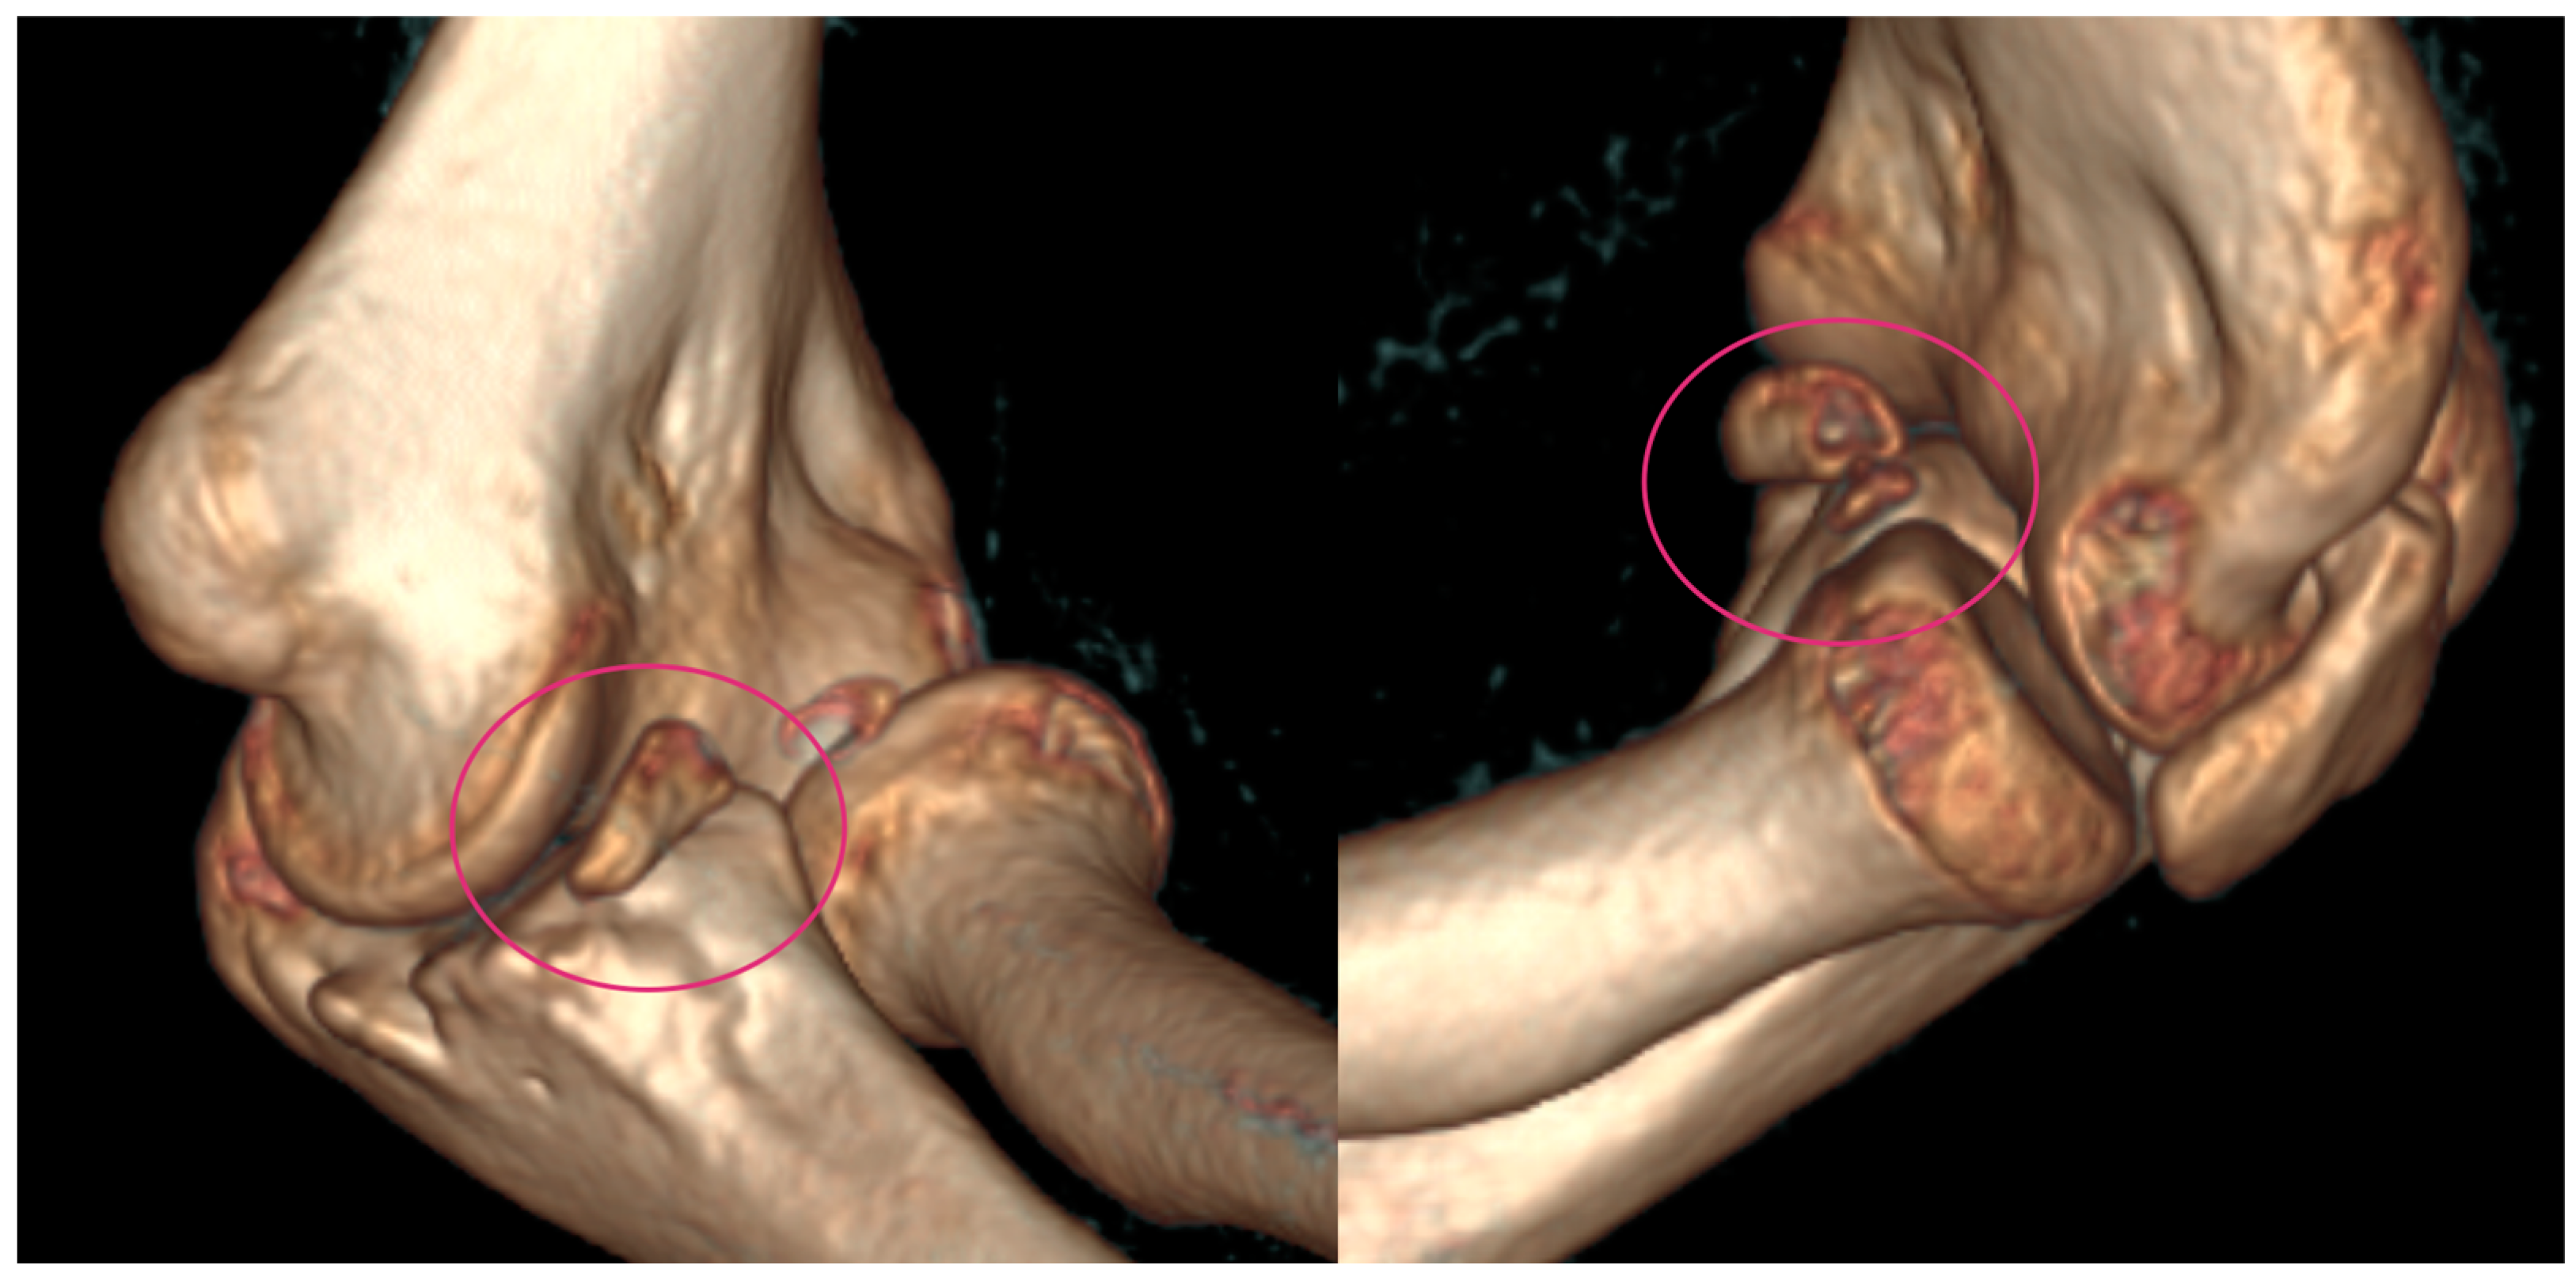

In 2020, her elbow dislocated once again when she was climbing onto her bed. In 2020, on the 1 October, she suffered a fall after she was pushed during a sports activity but had only pain and no dislocation, so she received a splint. A few days later, on the 7 October, spontaneous subluxation of the elbow occurred while the child was getting dressed. We applied a dorsal cast to prevent the extremity from suffering further dislocations and planned further static and dynamic diagnostic tests to evaluate the cause of the recurrent dislocations, as the root cause could not be identified on the initial CT or X-ray images that were provided in 2019 (Figure 2).

Figure 2. CT images were provided for surgical planning; the defect can be seen highlighted in the pink circle.